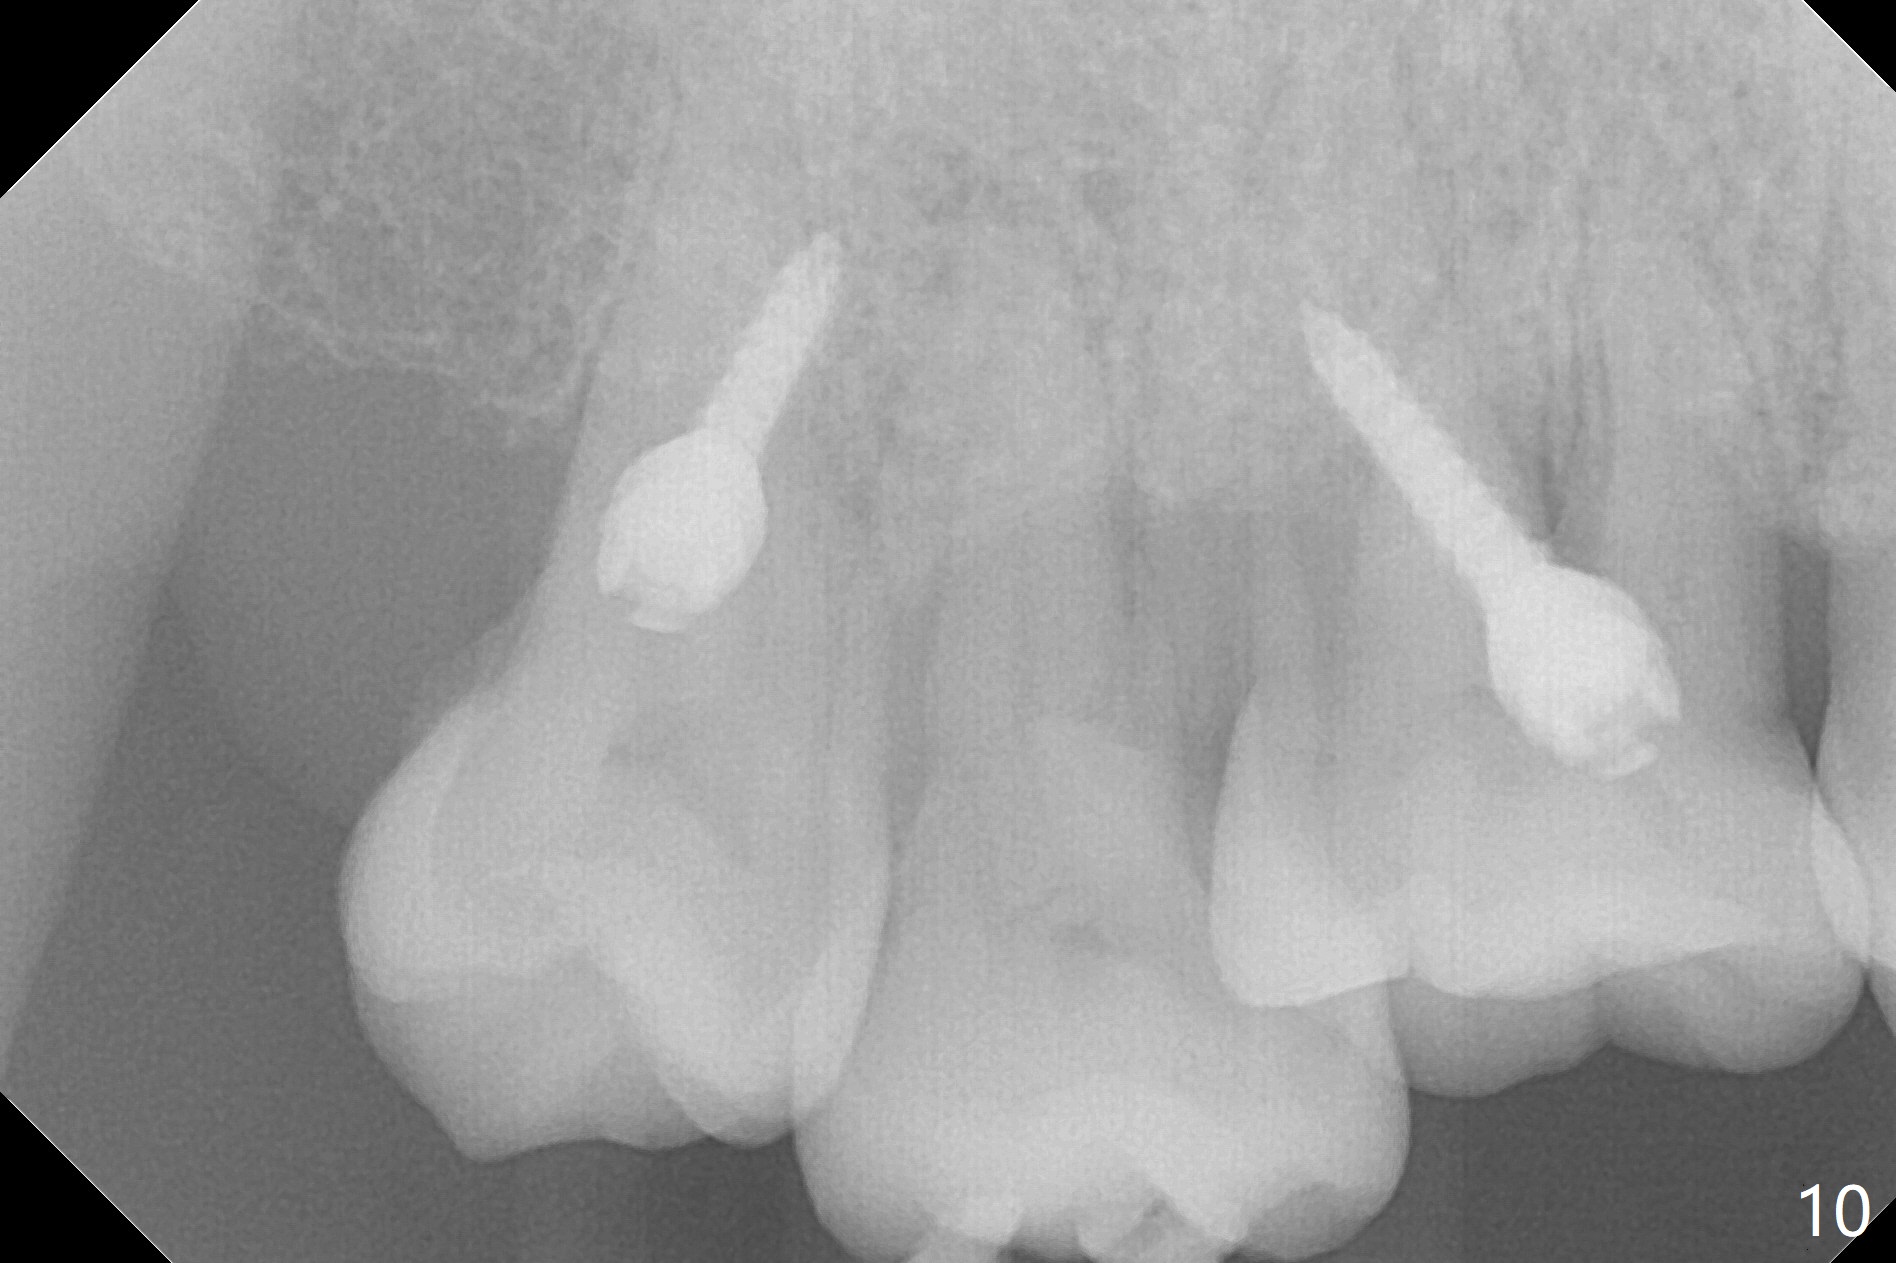

The buccal implant becomes loose in 2-3 months. When the wound heals (Fig.9 <), a 1.6x`10 mm implant is placed with the help of PAs for trajectory (Fig.10,11) and in the nonkeratinized gingiva (higher, the crestal bone may have been traumatized by previous implant placement, Fig.12). Two months later, the tooth #2 is partially intruded (Fig.13). A provisional (Fig.14 P) is fabricated in the osteointegrated implant at #31 with supraocclusion so that the remaining dentition has no occlusal contact (*). The periodontally compromised tooth #2 becomes in buccoversion in 2 months. The provisional is removed, while a lingual button is placed in the buccal surface of the tooth #2 (Fig.15). With power chain attached to the lingual mini-implant, the tooth #2 is lingualized in 2 months. The provisional and the implants are reused for final intrusion (Fig.16). The treatment is nearly 11 months. The buccal implant, although placed in the movable mucosa, remains stable and healthy (Fig.17). The tooth #1, as a guiding plane (to prevent #2 from distalization during intrusion), is not extracted after intrusion is completed.